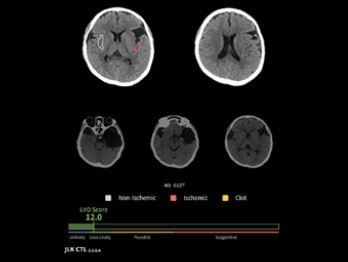

앞서 제이엘케이의 AI 솔루션 ‘JLK-CTL’은 식품의약품안전처 혁신의료기기 통합심사를 통과, 정식 승인을 받았다고 28일 밝혔다.

JLK-CTL은 조영제 없이 촬영한 비조영 CT(NCCT) 영상으로 대혈관 폐색(Large Vessel Occlusion, LVO) 여부를 신속하고 정확하게 예측하는 AI 솔루션이다. 응급 현장에서 주로 쓰이는 비조영 CT를 기반으로 조기에 대혈관 폐색 의심 환자를 선별해 골든 타임을 확보하는 것이 핵심이다.

이번 승인은 제이엘케이의 세 번째 혁신의료기기 통합심사 통과 사례로 회사는 앞서 지정을 받은 JBS-01K, JLK-LVO 등과 함께 비조영 CT(컴퓨터단층촬영), CTA(컴퓨터단층조영술), DWI(확산강조영상) 등 뇌졸중 진단에 필수적인 영상 분석에 비급여 처방을 할 수 있는 AI 솔루션 ‘3종 패키지’를 완성하게 됐다.

JLK-CTL을 활용하면 CTA, DWI 등의 정밀검사 대상을 신속하게 선별할 수 있고, 진단 및 치료 결정을 지원해 환자의 예후 개선에 기여할 수 있다. 또 불필요한 검사를 줄일 수 있어 환자의 치료비 부담 완화, 국가 보험재정 절감, 필수의료 체계 강화 등의 긍정적 효과도 기대된다.

제이엘케이 류위선 최고의학책임자는 “JLK-CTL은 대혈관 폐색 가능성을 정량적으로 제시해 의료진이 환자 치료 경로를 빠르게 결정할 수 있도록 지원한다”며 “뇌졸중 AI 솔루션 3종 패키지가 다양한 모달리티(영상 방식)를 지원해 병원 규모나 지역 차이 없이 균일한 분석 결과를 제공하는 등 필수의료 서비스 강화에 도움을 줄 수 있을 것으로 기대한다”고 말했다. 365mc 김남철 대표이사(왼쪽)와 라지엘테라퓨틱스 알론 블루멘펠드 대표이사/사진=365mc제공 365mc, 라지엘테라퓨틱스에 전략적 투자 … 지방감소 신약 ‘RZL-012’ 국내 3상 목전